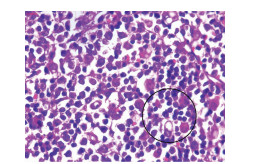

原发性肝淋巴瘤伴贫血和低蛋白血症1例报告

2021, 37(8): 1911-1913. DOI: 10.3969/j.issn.1001-5256.2021.08.034

摘要(963) HTML (226) PDF (2390KB)(53)

摘要: